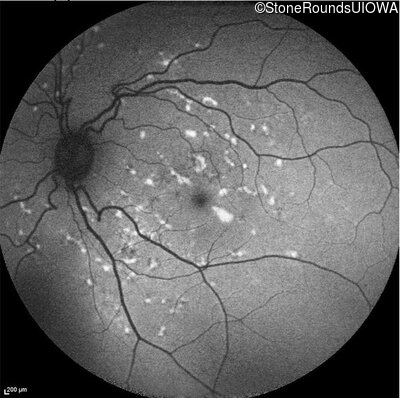

Visit at age: 39 years

Blue Autofluorescence - Right - 20/15

Exemplar